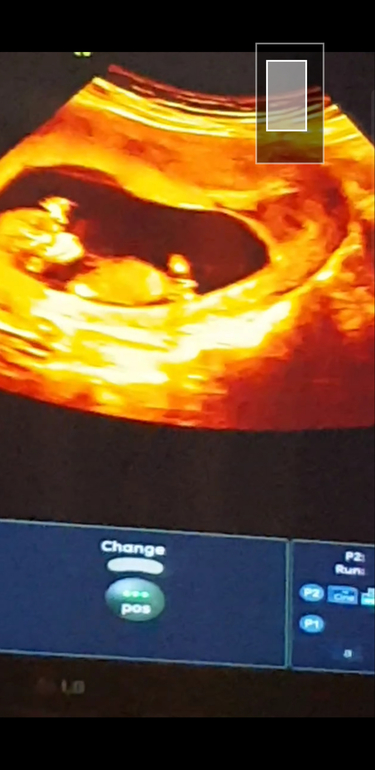

Вот сходила

Сегодня на узи , врач как я поняла пол не могла определить говорит не пойму рано ещё )